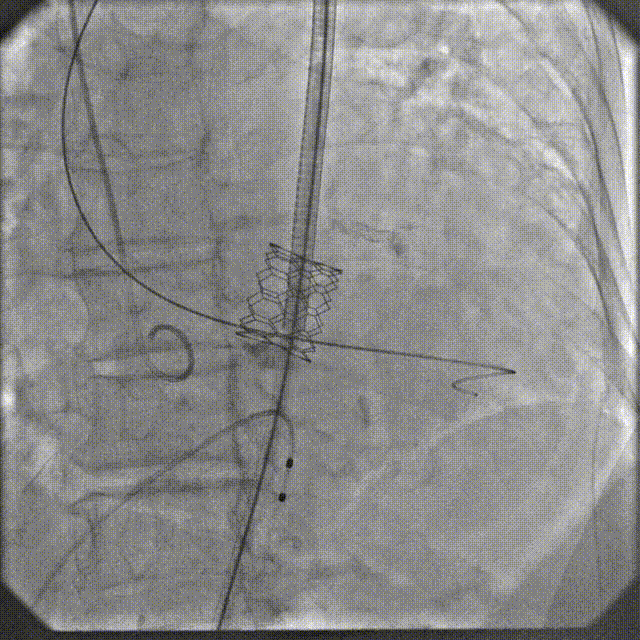

手术过程

根部造影

跨瓣

瓣膜系统过弓

定位造影

瓣膜确认位置后释放

回收极限处造影

最终造影

术后复查造影示瓣膜位置满意,形态良好,冠脉显影良好;TTE示轻微瓣周漏;排除入路血管问题,手术圆满成功。